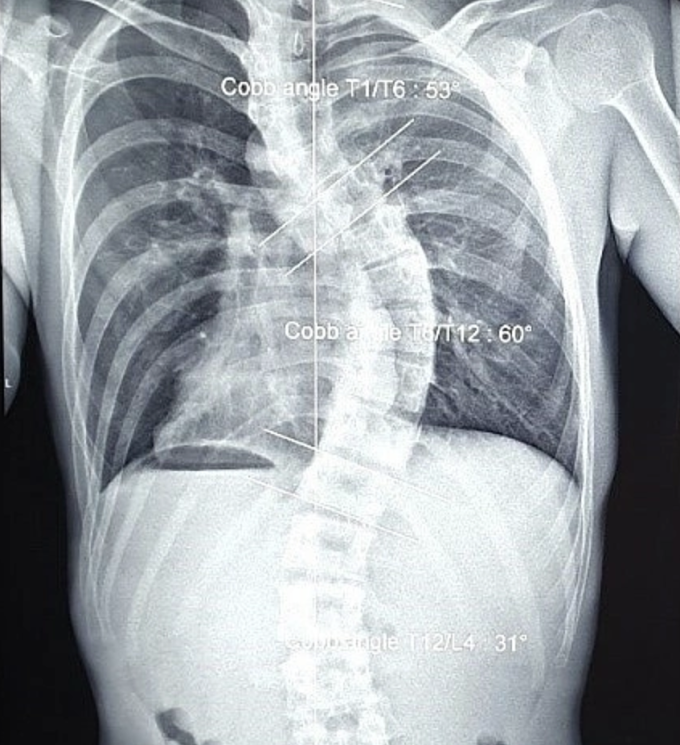

Thu, ở TP HCM, cũng chịu hậu quả tương tự. Bố mẹ phát hiện cô bị cong vẹo cột sống từ năm lớp 7 nhưng không đưa đi điều trị. Từ đó đến khi trưởng thành, Thu thường xuyên đau mỏi vùng lưng, khó thở, không thể leo nhiều tầng lầu. Sau 10 năm sống chung với bệnh, cô đi khám. Bác sĩ Calvin Q Trịnh, Giám đốc Đơn vị Phục hồi chức năng và hình thể HMR, chẩn đoán Thu bị vẹo cột sống ngực thắt lưng nặng, mất độ ưỡn sinh lý cột sống cổ, các đốt sống ngực đã biến dạng.

Ảnh X-quang đốt sống ngực của Thu bị biến dạng nặng, không thể điều trị lấy lại được hình dáng ban đầu. Ảnh: Bác sĩ cung cấp